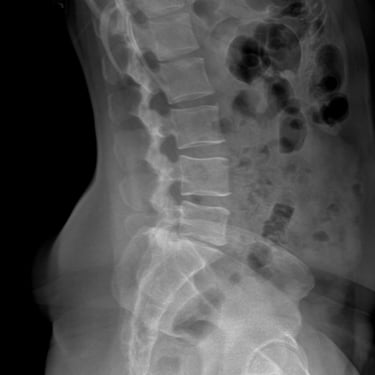

Manejo quirúrgico de la hernia lumbar con inestabilidad: enfoque moderno con FTP y TLIF

La hernia lumbar con inestabilidad vertebral es una patología frecuente que causa dolor lumbar persistente, ciática y limitación funcional, afectando la calidad de vida del paciente. Cuando el tratamiento conservador no logra resultados adecuados, la cirugía se convierte en la mejor opción terapéutica. La fijación transpedicular con tornillos (FTP) junto con la técnica TLIF (Transforaminal Lumbar Interbody Fusion) permite estabilizar la columna, descomprimir las estructuras nerviosas y lograr una adecuada fusión ósea. Este abordaje, especialmente mediante técnicas mínimamente invasivas (MISS), ofrece múltiples beneficios, como menor daño muscular, menor dolor postoperatorio y recuperación más rápida, facilitando el retorno temprano a las actividades cotidianas con mejores resultados clínicos.